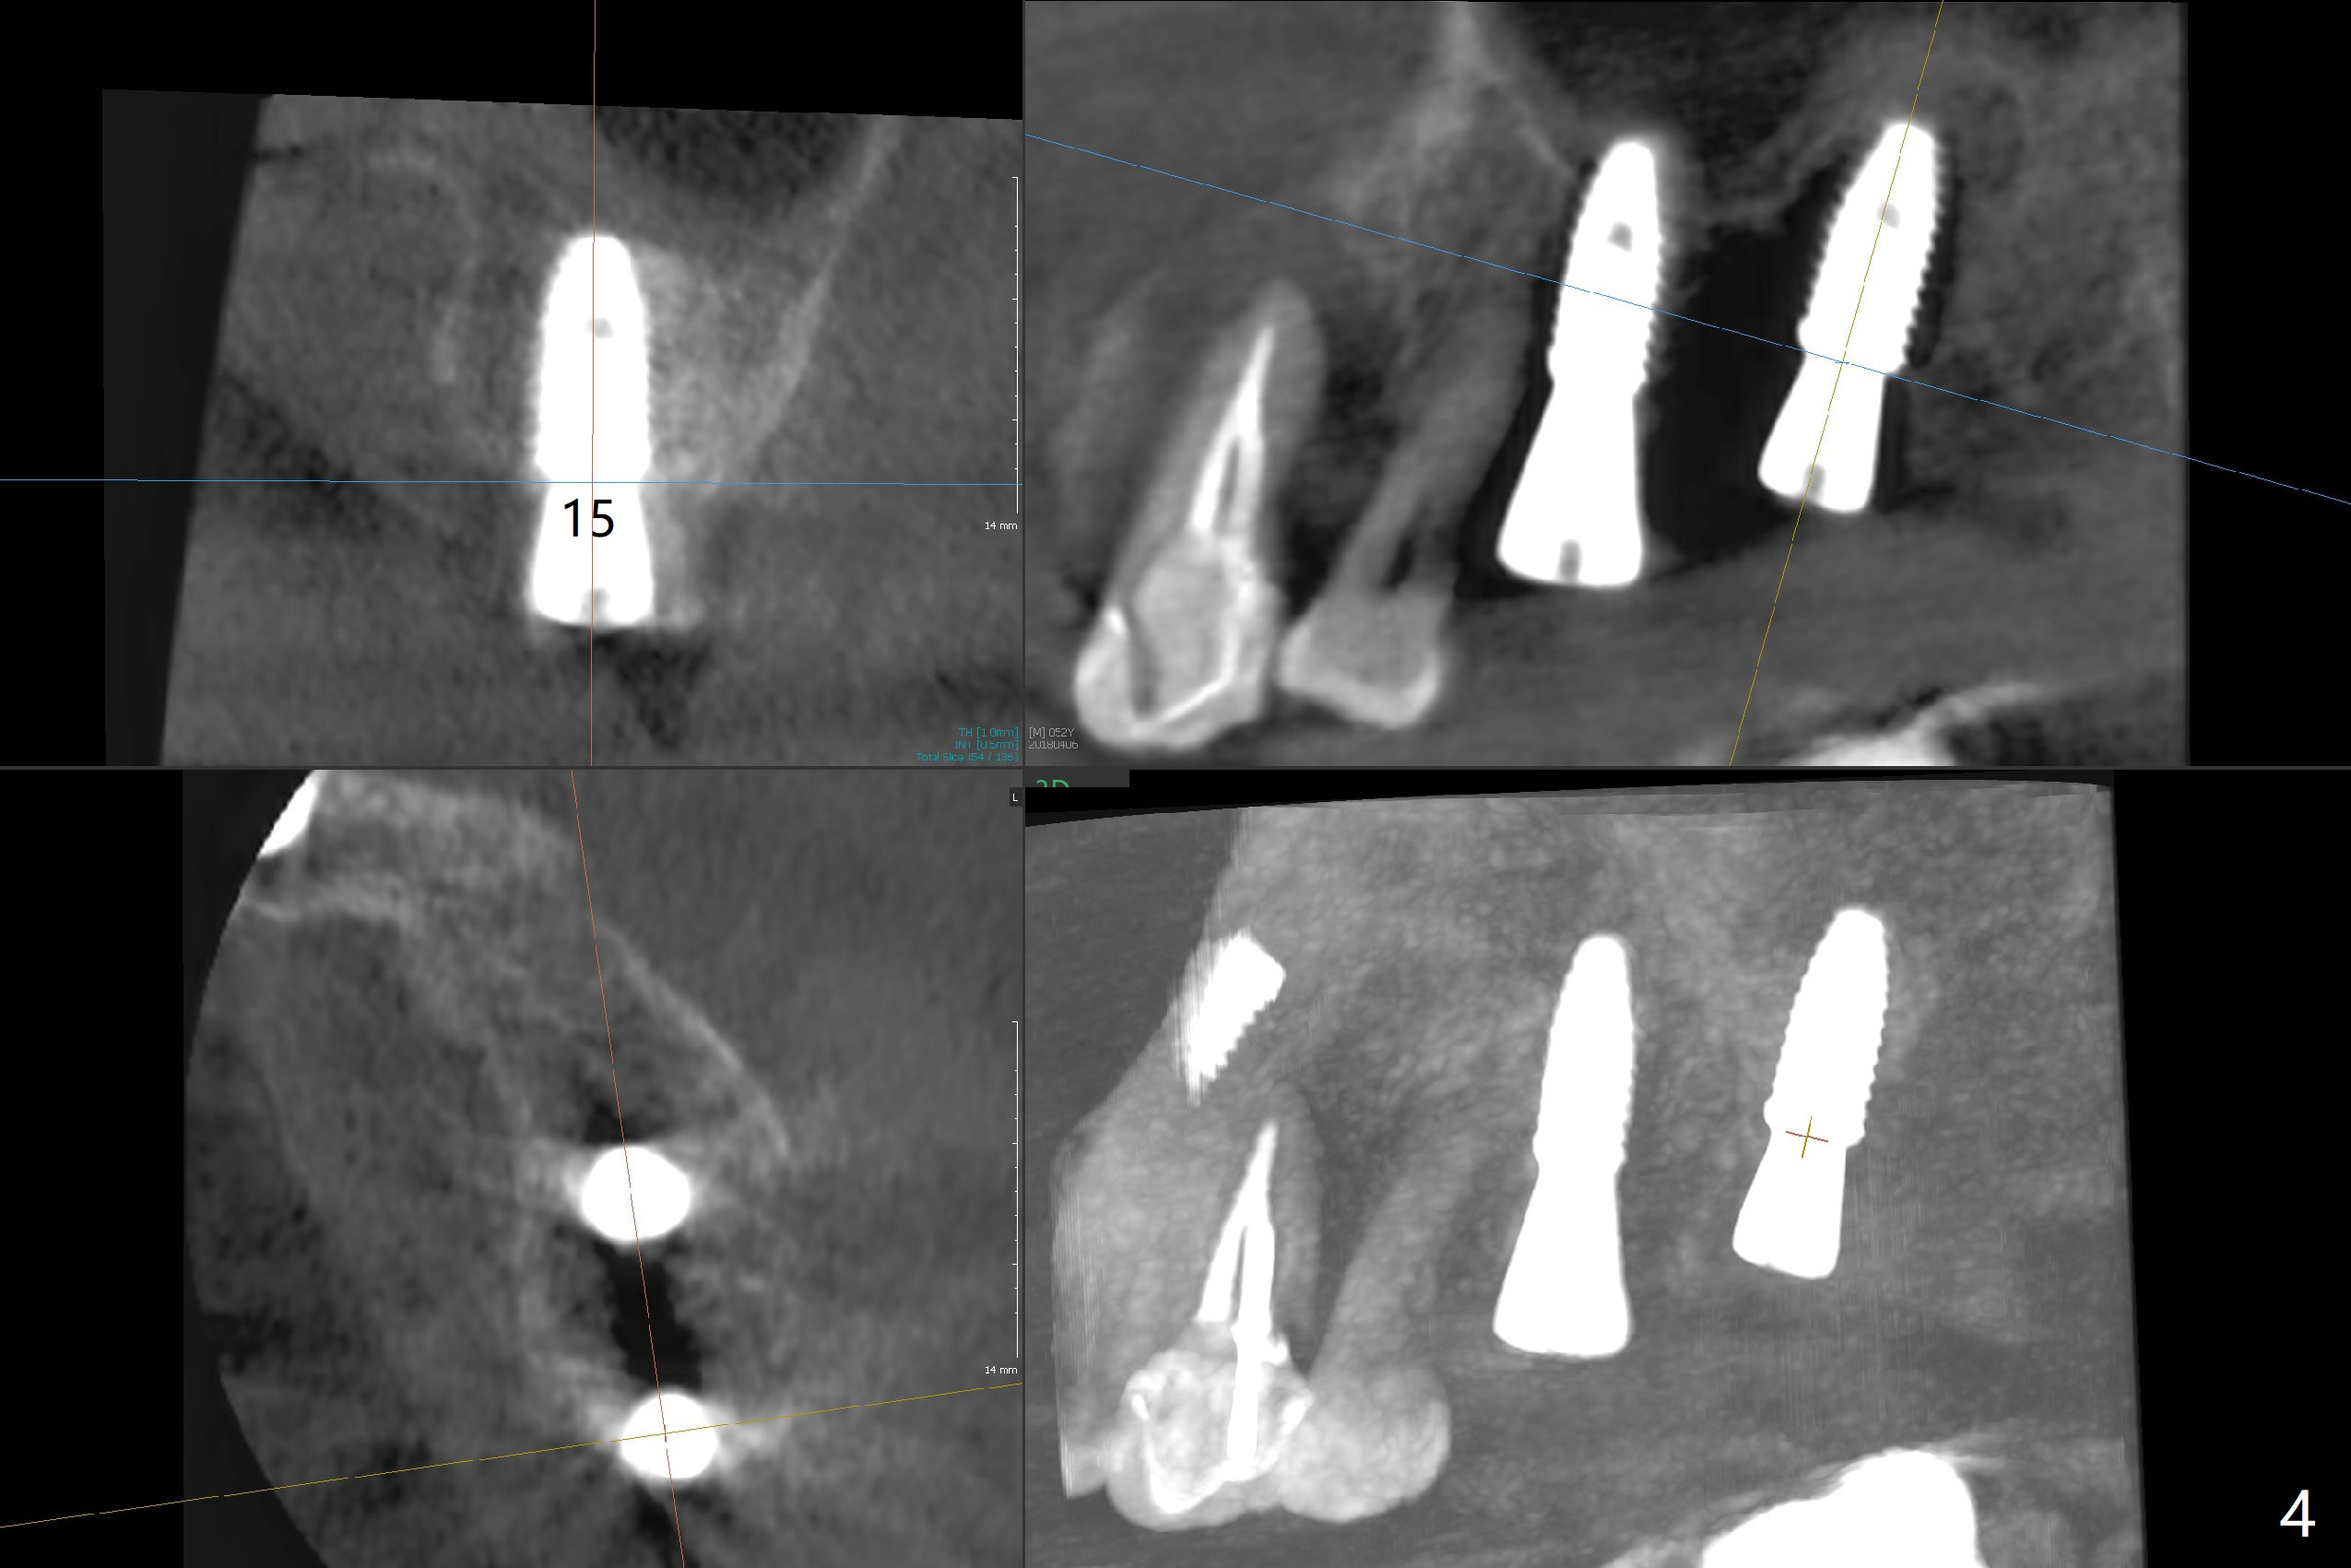

Immediately postop PA (Fig.1) and panoramic X-ray (Fig.2) show that the implant at #14 is close to the root of the tooth #13.  Clinic exam and CBCT (Fig.3,4) demonstrate a reasonable separation.  The trajectory of #14 osteotomy may be altered while using 2.8 mm round drill for 7-9 mm for sinus lift (free hand).  There is no bone loss 8 months postop (Fig.5).

#15 looks good as planned and #14 seems quite close to the neighboring tooth and quite off from the planed position.

I followed the steps faithfully.  As CT indicates, the implants are pretty parallel to each other.  The suspected step is sinus lift using reamer (free hand).  Initially I placed the drill pretty parallel to the crown #13.  Later more or less oblique.  When the guide returned, I had no option other than to follow the guide.  If the implant really touches the root, can I redirect free hand?